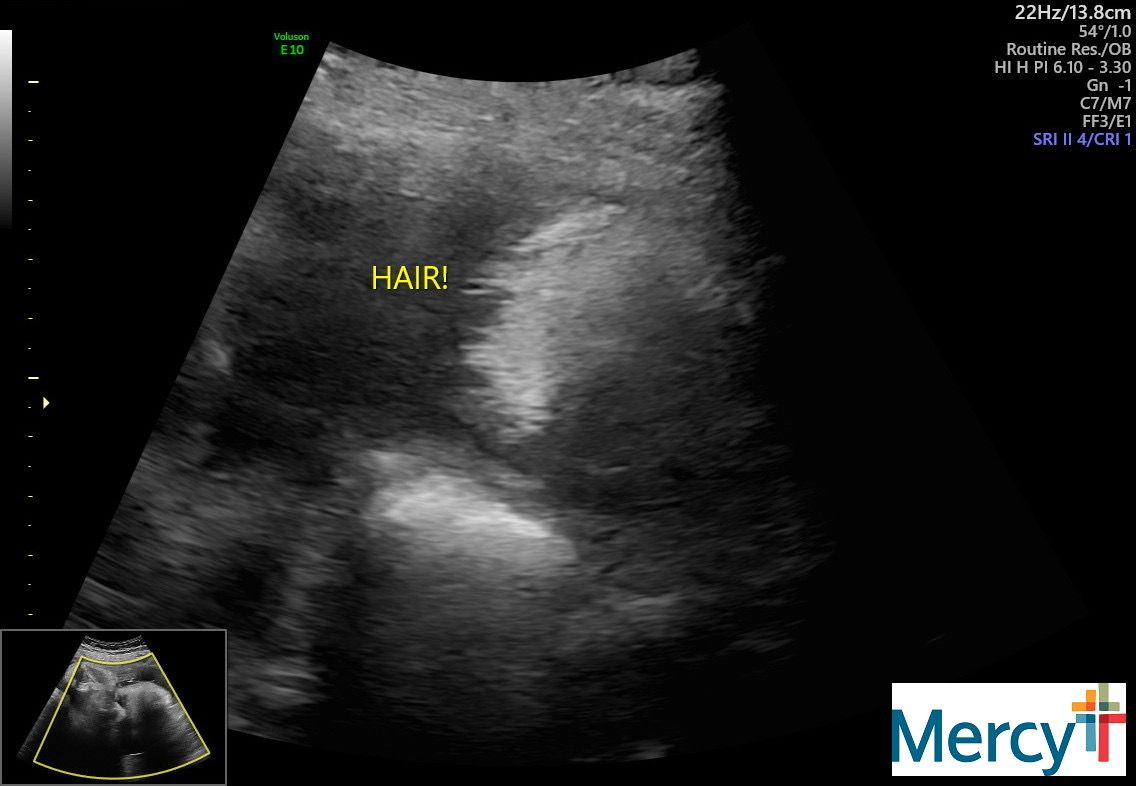

I am still going to the hospital twice a week to do a NST and an ultrasound for fluid levels. It's been pretty uneventful! The tech today told me he has a lot of hair. Yay!

Our final NST + ultrasound!!!